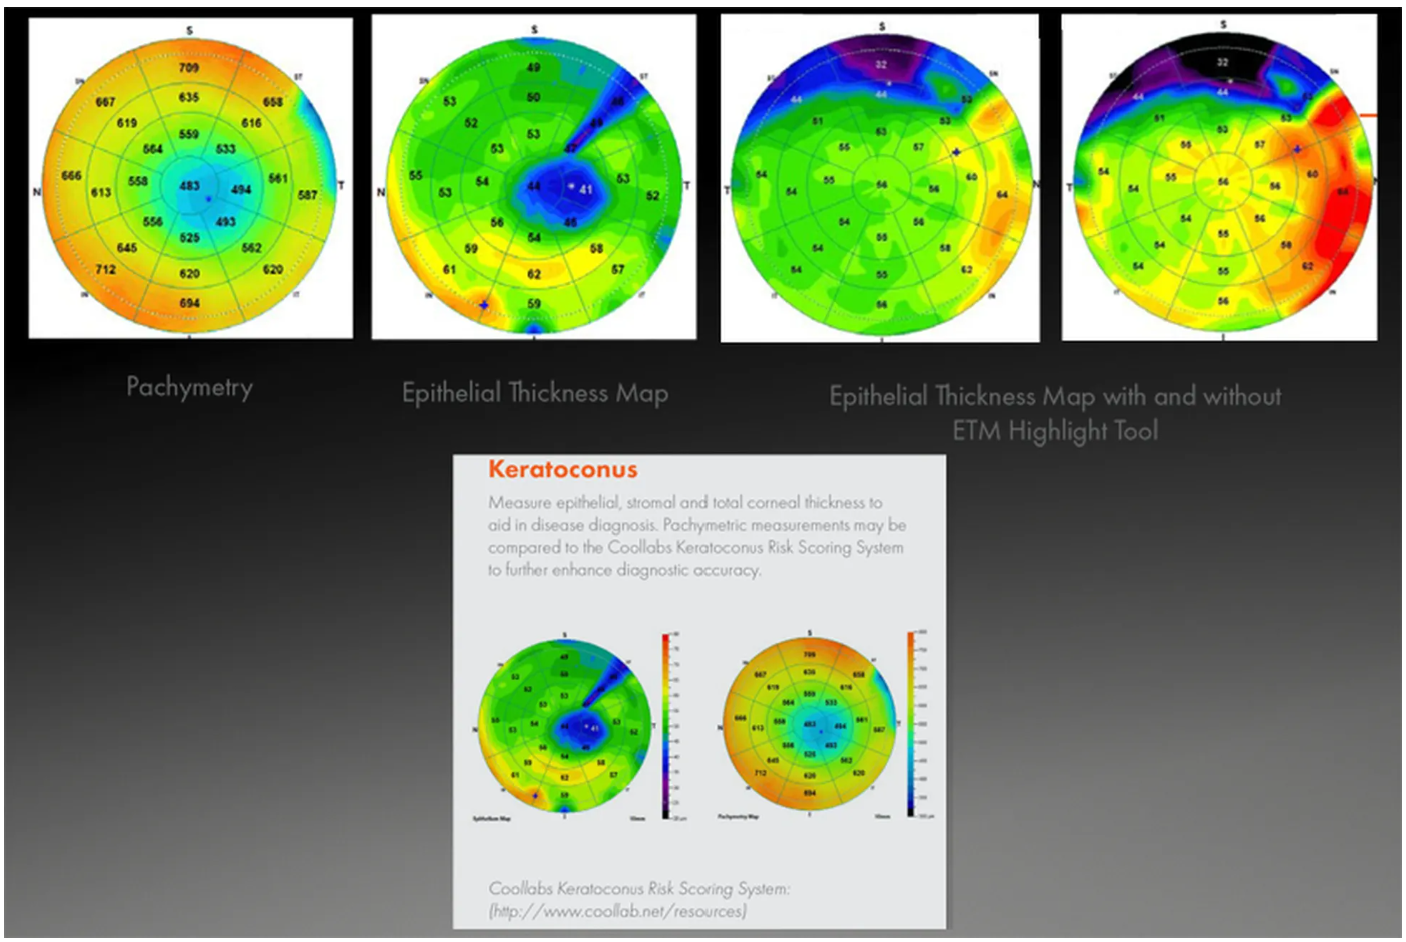

- Оптическая пахиметрия, картирование эпителия и стромы роговицы в зоне диаметром 10 мм.